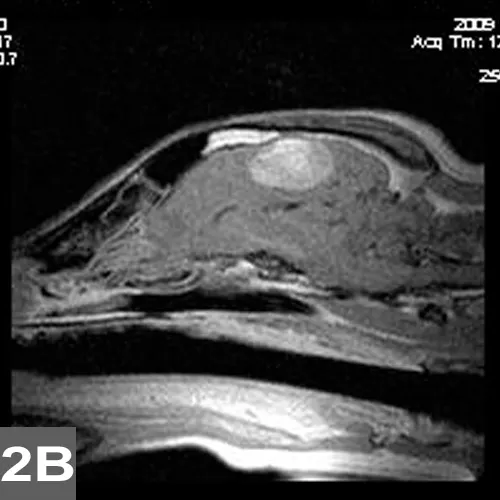

Initial diagnostics typically consist of emergency blood analysis (ie, glucose, electrolytes, blood gases, urea concentration, PCV/TS), but a more complete blood analysis (ie, CBC, chemistry panel, thyroid profile), urinalysis, additional screening tests (eg, thoracic radiography, ECG, abdominal radiography or ultrasonography), and blood pressure monitoring are often recommended. Other pertinent tests (eg, blood ammonia or bile acids, coagulation profile, insulin level, toxicologic and infectious disease diagnostics) depend on the suspected underlying disease and should be considered before pursuing advanced imaging (eg, MRI; Figure 2) and cerebrospinal fluid analysis.

Postgadolinium T1 axial (2A) and sagittal (2B) MRIs of a dog with a brain tumor